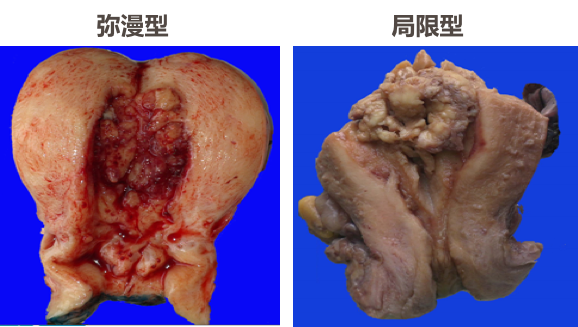

(1)肉眼观,子宫内膜癌分为弥漫型和局限型。弥漫型表现为子宫内膜弥漫性增厚,表面粗糙不平,灰白质脆,常有出血坏死或溃疡形成,并不同程度地浸润子宫肌层。局限型多位于子宫底或子宫角,常呈息肉或乳头状突向宫腔。如果癌组织小而表浅,可在诊断性刮宫时全部刮出,在切除的子宫内找不到癌组织。